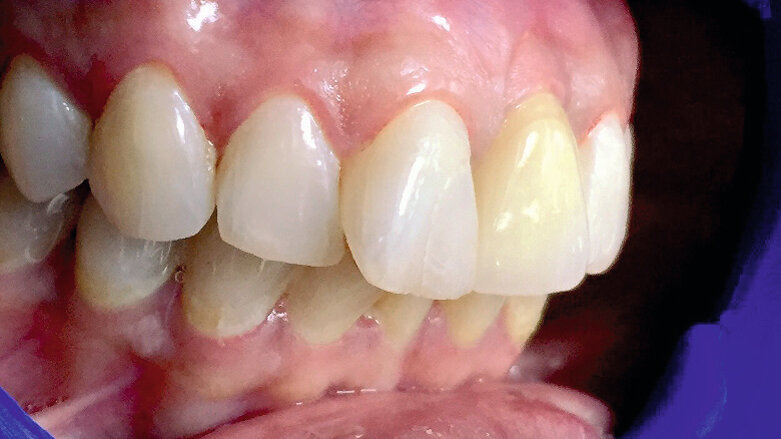

La patiente, âgée de 36 ans, nous a consulté pour un contrôle dentaire en raison d’une douleur dans la région des dents antérieures supérieures gauches. À ses dires, la douleur commençait subitement et s’aggravait lors de la mastication. L’examen clinique de l’incisive centrale supérieure gauche (dent 21) a révélé une inflammation, une douleur à la percussion et une fracture de la dent au niveau de la limite cervicale. La dent avait fait l’objet d’un traitement endodontique trois ans plus tôt et n’avait jamais été restaurée auparavant. Une radiographie a montré une couronne fracturée touchée par une résorption radiculaire mineure ainsi qu’une infection périapicale (Figs. 1a–c). L’examen radiographique comme l’examen clinique ont également confirmé la présence d’une largeur et d’une hauteur d’os suffisantes. Le pronostic très défavorable d’un retraitement endodontique a été expliqué à la patiente et elle a opté pour un traitement plus radical. La décision d’extraire la dent et de la remplacer immédiatement par un implant monobloc en zircone a donc été prise.

Fig. 1a : Photographie clinique préopératoire de la dent 21.